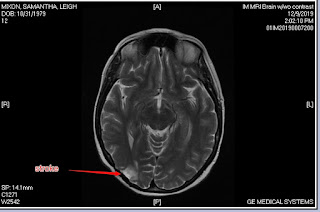

However, recently I've had two vascular strokes so am going to acquire another specialist for this (honestly have no idea how many I have now).

One of the strokes left a lot of pain in my right foot on the bottom. I've been doing physical therapy for it, so it's getting better. I once thought this lung cancer would be the only thing to take me out. Now I'm having other issues, like strokes, so maybe it won't be lung cancer.